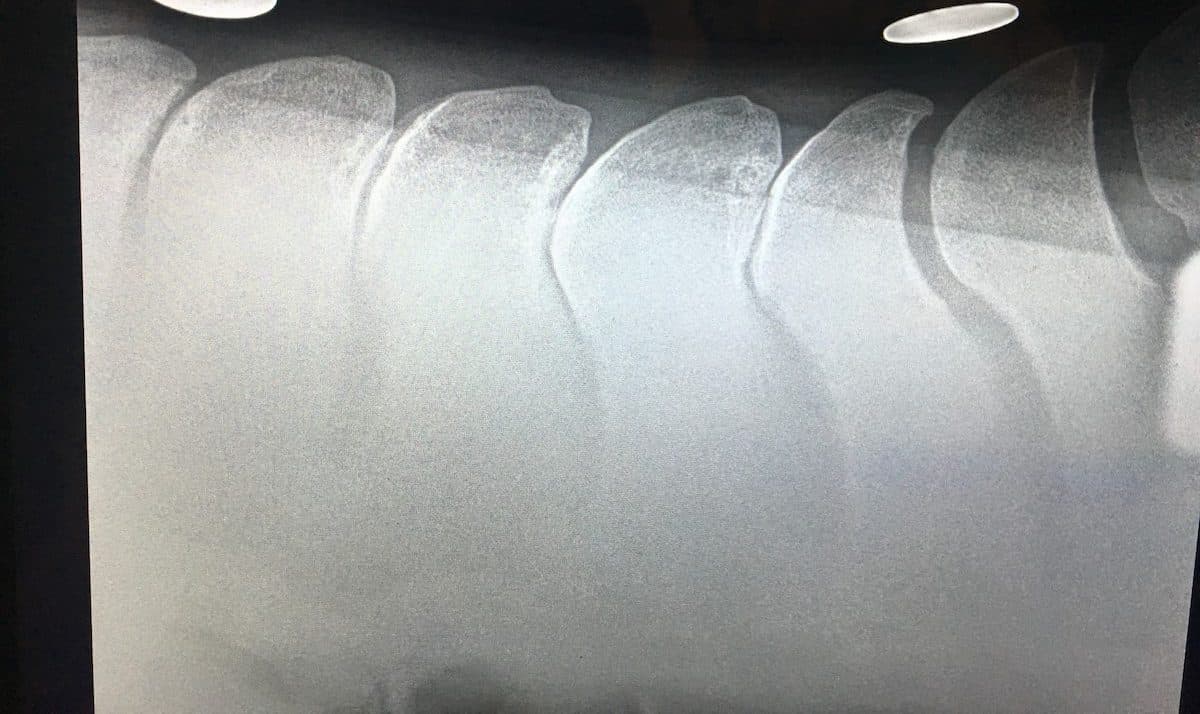

Kissing spines occurs when the vertebrae’s dorsal spinous processes touch. Courtesy The Horse Staff

Kissing spines This condition occurs when the vertebrae’s dorsal spinous processes are spaced too closely or touch. While many affected horses exhibit signs of back pain, some show no signs of discomfort or diminished performance. Veterinarians can use radiography to diagnose the condition and can recommend the best treatment option, such as corticosteroid injections or surgical correction.